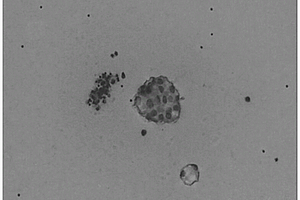

本发明公开了一种操作简单、高通量光致电化学生物传感器并成功用于同时检测三种癌细胞。首先通过金纳米自催化还原在纸纤维表面修饰一层金纳米颗粒,然后在长金修饰的纸工作电极表面制备硫化镉‑石墨烯‑氧化锌棒三元复合材料,作为光电极,利用化学发光替代传统氙灯,通过控制化学发光反应顺序依次激发光电极,通过依次检测三个光电流峰值,实现对三种癌细胞的同时检测。